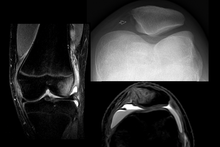

| Radiograph of a patient with patellar dislocation. Normally the patella projects over the distal femur. | |

Patellar dislocation is an injury of the knee, typically caused by a direct blow or a sudden twist of the leg.[1] It occurs when the patella (kneecap) slips out of its normal position in the patellofemoral groove, and generally causes intense pain with swelling of the knee.[1] Open or arthroscopic surgery may be used to repair damage, but are typically avoided since rates of re-injury, knee function, and patients' opinions do not differ much from conservative treatment.[2][3][4]

The patella generally dislocates laterally, and can be accompanied by acute pain and disability. Immediate reduction can be accomplished by hyperextension of the knee, and by providing a medialward pressure to move the patella back into the patellofemoral groove. Hyperextension of the knee on its own could possibly move the patella into place, because this motion locks the knee in place. When the knee is locked the ligaments are twisted and taut, allowing the muscles involved to relax and the patella to slide back into place.[5] If that does not work, a medical professional must manually perform an orthopedic reduction.[1] Swelling and impaired mobility follow patellar dislocation,[6] and a rehabilitation program of six to sixteen weeks is recommended whether or not the patient undergoes surgery.[3]

To assess the knee, a clinician can perform the patellar apprehension test by moving the patella back and forth while the patient flexes the knee at approximately 30 degrees.[6]

The patient can do the patella tracking assessment by making a single leg squat and standing, or by lying on his or her back with knee extended from flexed position. A patella that slips medially on early flexion is called the J sign, and indicates imbalance between the VMO and lateral structures.[14]